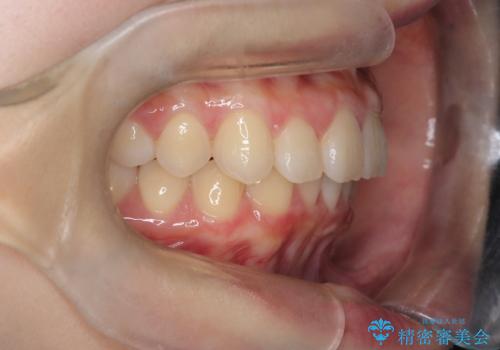

- 前歯が出ていることを主訴に来院されました。

下顎前歯が1本欠損していることもあり、前突はある程度残ることを説明し、インビザラインにて治療を行いました。

今回は抜歯矯正ではなく歯列弓の拡大とIPR、遠心移動を行って配列することができました。

口元も改善し患者さんには喜んでいただけました。

下顎前歯が1本少ないため、上下の正中は合いません。